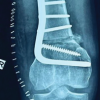

X-rays of the left knee confirmed a well-fixed total knee prosthesis (Fig. 3) without any implant loosening. Given the stable implant, a posterior soft tissue release was chosen to address the flexion contracture. Unfortunately, prior conservative measures, including physiotherapy, bracing, and traction, proved ineffective in improving knee flexion. Therefore, surgery was deemed necessary to correct the deformity. The other option would have been a revision of the total knee prosthesis to increase the extension gap. It was anticipated that an extensive posterior release would be required after isolating the critical neurovascular structures for which plastic surgical help was sought. The plastic surgery team was also involved in the decision-making in anticipation of difficulty in soft tissue closure following the release. Under general anesthesia with the patient in the prone position and under tourniquet control (total tourniquet time-11/2 h), the previous posteromedial longitudinal surgical scar was incised and extended distally over the proximal third leg region. The popliteal artery, tibial nerve, and common peroneal nerve were identified and isolated (Fig. 4) by the plastic surgical team aided by magnification. The hamstrings (medial and lateral) and posterior capsule (prosthesis was visualized) were incised and released through the two windows on either side of the popliteal artery. The medial gastrocnemius was also erased from origin on the medial femoral condyle. Partial release of the medial collateral ligament and posterior cruciate ligament was done. The biceps femoris was cut at the level of insertion. The short saphenous vein, sural nerve, and saphenous vein were sacrificed to facilitate exposure. Following the release, the knee could be easily extended to near full extension (Fig. 5). Following the dissection of soft tissues, closure was done by the plastic surgical team. Z-plasty of the skin was done to facilitate closure (Fig. 6 and 7). The drain was placed in situ. The leg was splinted with an above-knee splint, both anteriorly and posteriorly.